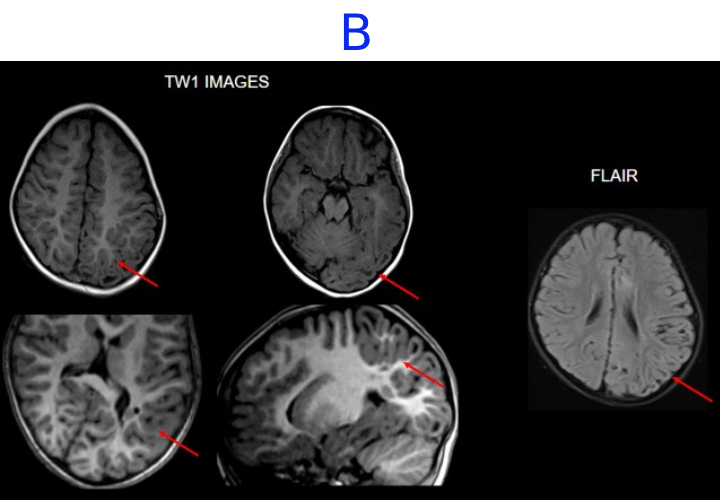

A. FINDINGS: MRI BRAIN WITH IV CONTRAST

• A. There is hemihemimegelencephaly in the left parieto-temporo-occipital lobes, characterized by enlargement of the involved hemisphere. There is associated gyral thickening with white matter signal changes in the adjacent subcortical white matter.

• B. Areas of rarefaction are seen in white matter signal changes. Note is also made of periventricular nodular heterotropia along the atrium of the left lateral ventricle.

Left posterior quadrantic dysplasia with associated subcortical white matter signal abnormalities and periventricular nodular heterotropia.